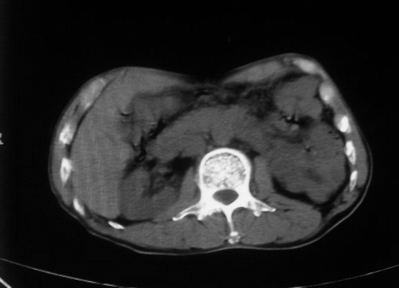

男,66岁,贲门ca术后一年,喝了5、6杯水了。怎么描述跟诊断啊